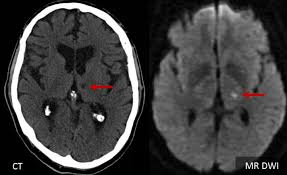

Lacunar strokes happen when tiny arteries—sometimes no wider than a hair—become blocked deep inside the brain. Unlike larger strokes, lacunar strokes often produce no dramatic symptoms at first. Research published in journals like Stroke and Neurology shows that 20-30% of adults over 60 have evidence of silent lacunar strokes on brain imaging, even when they feel perfectly fine.

Over time, repeated lacunar strokes create small cavities in critical areas such as the basal ganglia, thalamus, and white matter tracts. The gradual buildup can affect walking, balance, memory, and bladder control—robbing people of confidence and daily independence without any obvious alarm bells.